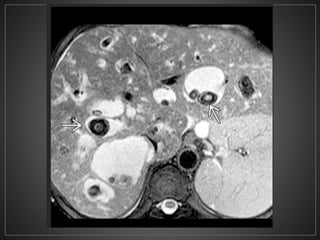

CPRE: Dilataciones saculares de CBIH. TC: Simple:Áreas redondas, hipointensas en topografía de CBIH. Contraste: Signo del punteado central. RM: T2: Espacios quísticos hiperdensos

• #50 SIGNO DEL PUNTEADO CENTRAL: Pequeños puntos resaltados dentro de los conductos biliares intrahepaticos dilatados.

• #53 El CT axial con contraste muestra una dilatación masiva de los conductos biliares intrahepáticos. punto "central" o "excéntrico" en muchas de las estructuras quísticas, que representan las venas portas, un clásico hallazgo de imágenes en la enfermedad de Caroli.

• #55 Axial T2WI MR muestra dilatación sacular de los conductos biliares intrahepáticos, muchos de los cuales contienen grandes cálculos hipointensos (flechas)